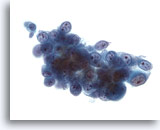

Figure 45

Voided urine, low grade carcinoma

The cells in the clusters of low grade urothelial carcinoma have high N/C ratios. 60x

Voided urine, low grade carcinoma

The cells in the clusters of low grade urothelial carcinoma have high N/C ratios. 60x

Figure 45

Voided urine, low grade carcinoma

The cells in the clusters of low grade urothelial carcinoma have high N/C ratios.

60x

Voided urine, low grade carcinoma

The cells in the clusters of low grade urothelial carcinoma have high N/C ratios.

60x